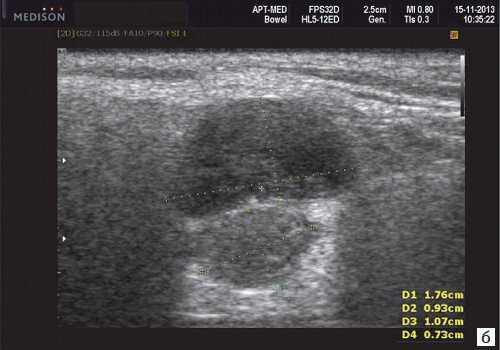

Плеоморфная (полиморфная) аденома (смешанная опухоль СЖ) - аденома СЖ, построенная из двух типов клеток: эпителия протоков и миоэпителиоцитов. Макроморфологическая картина. Опухоль обычно представляет собой эластичный или плотный узел дольчатой серовато-белой ткани, как правило, инкапсулированный частично. Типичной для плеоморфной аденомы является так называемая хондроидная строма, напоминающая гиалиновый хрящ. Варианты эхографического изображения плеоморфных аденом представлены на рисунке 8.

Рис. 8. Плеоморфная аденома СЖ.